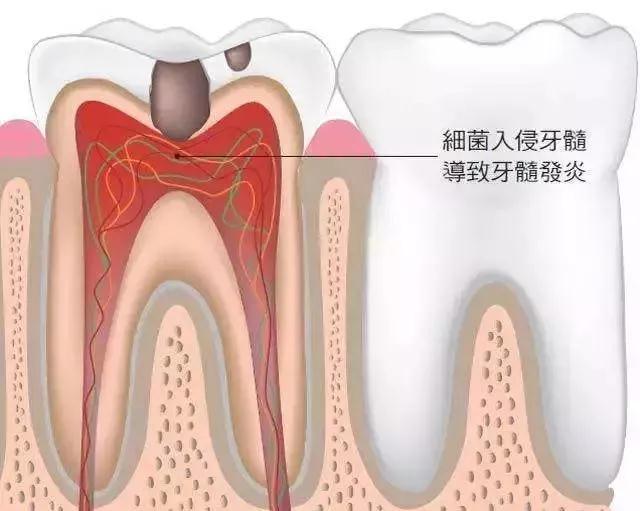

至于牙髓炎,相信大家都知道,这个病就是牙髓组织的牙髓炎的炎症。牙髓是由于神经血管结缔组织,牙髓的位置在牙齿内部的牙髓腔内。牙齿硬组织疾病如果得不到及时有效的控制和治疗,很可能会引发牙髓炎,成为口腔最常见的疾病之一。那么,你知道如何正确区分牙髓炎吗?下面给大家介绍一下鉴别牙髓炎的方法。1.牙髓炎的症状1。深龋、可逆性牙髓炎、慢性牙髓炎(1)有疼痛症状时可有冷热痛,但深龋、可逆性牙髓炎的牙齿无自发性疼痛史;慢性牙髓炎可有自发性疼痛史。

其实牙髓炎这种病是有一定原因的,是上火引起的,因为上火会导致身体各项功能的下降,为病毒感染创造了一定的环境。日常生活中,引起牙髓炎的因素比较复杂,牙髓炎的具体因素需要和专家做好沟通。1.牙髓炎的原因(1)牙髓炎疾病的形成主要是由于感染。任何病毒侵入人体后,都会对身体造成一定的伤害。任何原因引起的细菌及其毒素都会侵入髓腔,引起牙髓的炎症。